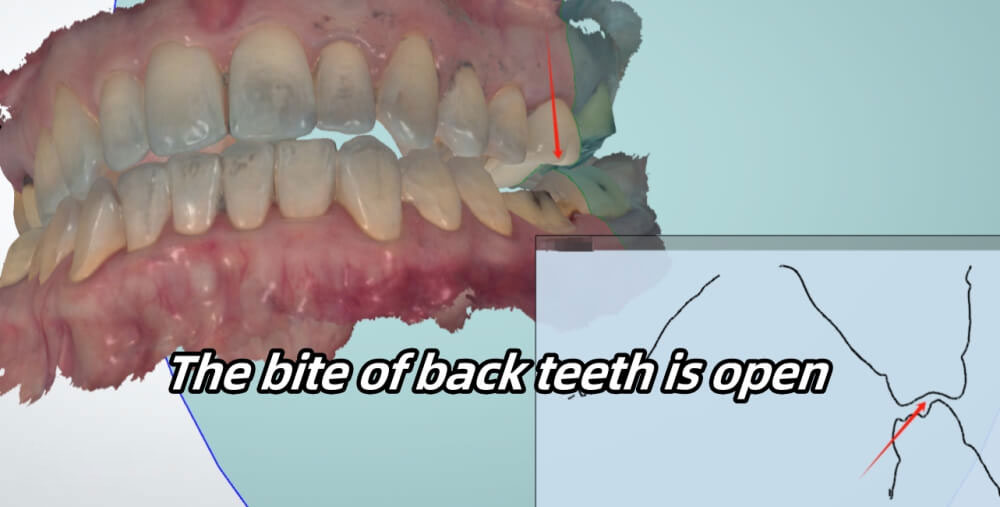

In this case, the upper front teet can touch the lower front teeth. However, the upper back teeth cannot touch the lower back teeth.